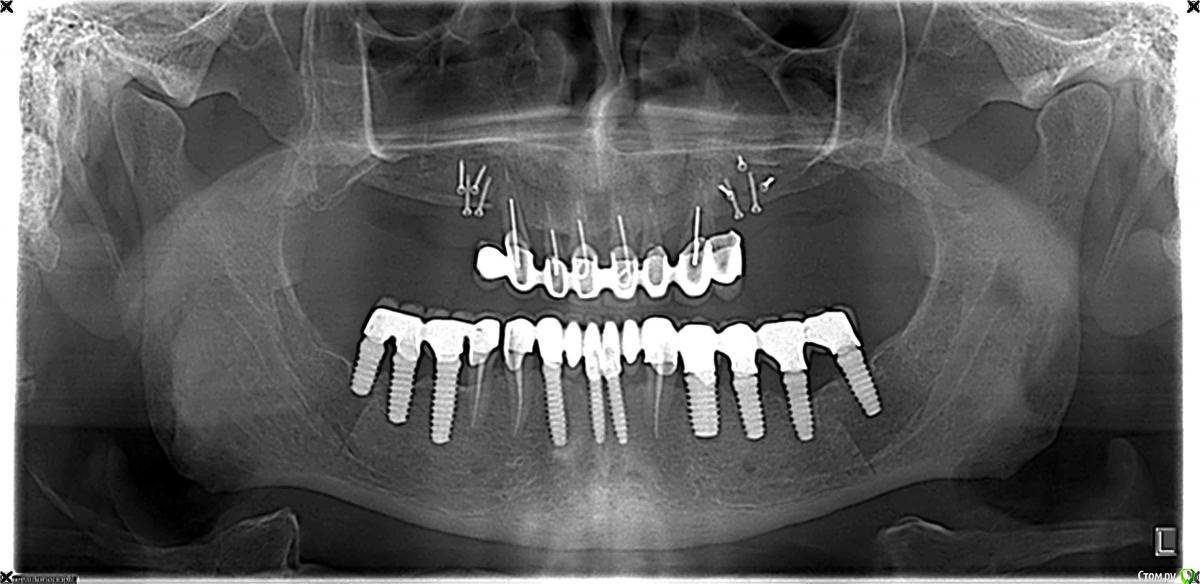

SergeyAL Опубликовано 11 сентября, 2015 Автор Поделиться Опубликовано 11 сентября, 2015 на первом этапе была проведена костная пластика по Кури в 1 и 2 квадрантах + двухсторонний синуслифт, доступ вертикальный тоннель. врменная реставрация на остатках зубов во фронтальном отделе.через 5 месяцев зубы подвели, пришлось проводить удаление зубов, одномоментную имплантацию, установку временных имплантатов во фронтальнос участке и фиксировать временную конструкцию на временных имплантатах.через 4 месяцараскрытие имплантатов с пластикой кератинизированной десны СДТвременное протезирование на постоянных имплантатахчерез 3 месяца постоянное протезирование на имплантатах последний снимок через 8 месяцев после постоянного протезирования. 4 Ссылка на комментарий